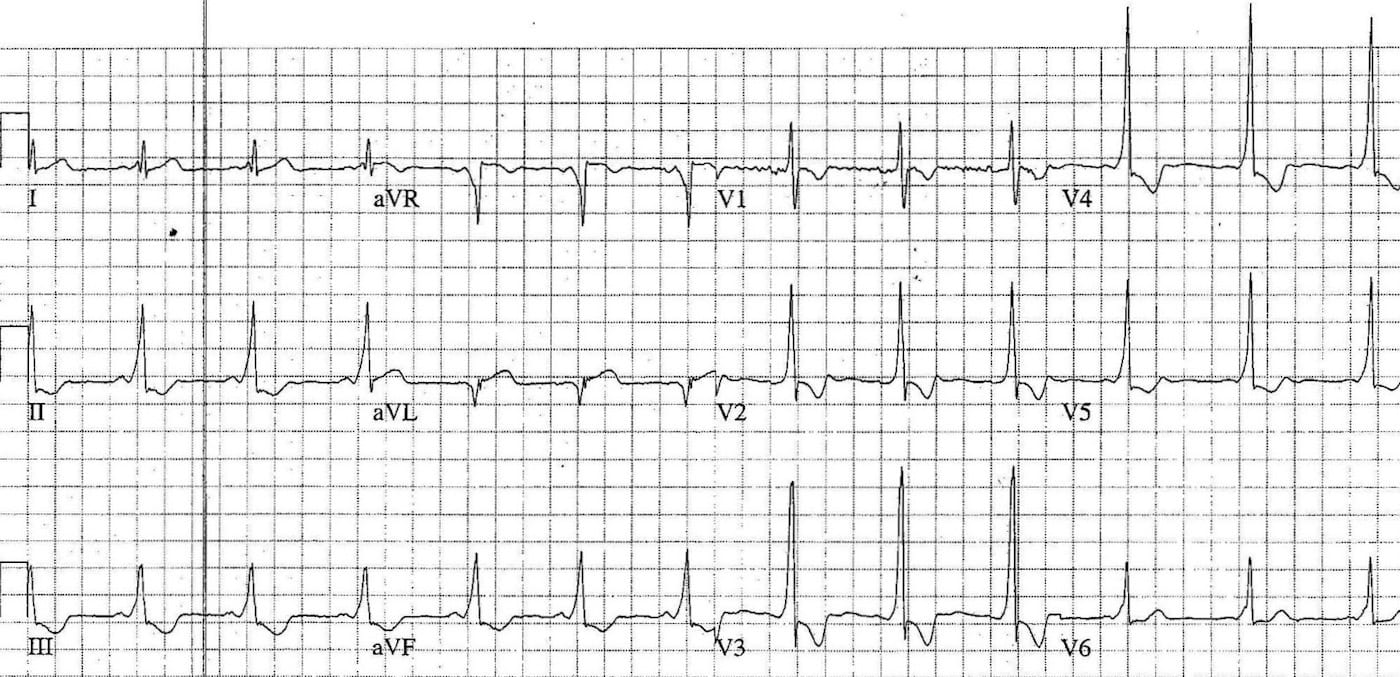

This is an ECG of monomorphic VT. Note the very regular, broad complex tachycardia and the same QRS morphology throughout.

https://litfl.com/ventricular-tachycardia-ecg-library/

© Life in the Fast Lane. Licensed under CC BY-NC 4.0

This is an ECG of polymorphic VT (specifically, Torsades de Pointes – a type of polymorphic VT). The varying QRS morphology can be appreciated, with the characteristic morphology of QRS complexes “twisting” around the isoelectric line.

https://litfl.com/torsades-de-pointes-ecg-library/

© Life in the Fast Lane. Licensed under CC BY-NC 4.0